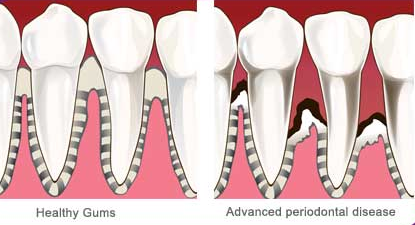

Healthy teeth depend heavily on healthy gums for support. Gum disease causes infections, sensitivity and eventual loss of teeth.

Gum disease (or periodontal disease) is usually caused by the build up of plaque which hardens and becomes tartar. This causes an irritation to your teeth and gums, resulting in an inflammatory reaction to the bacteria that is present. This can eventually lead to the loss of your teeth.

- Receding Gums – Teeth appear longer due to decreased gum over the tooth

- Gaps – Spaces appear between the teeth and teeth begin to drift

- Loose Teeth – Teeth become progressively looser